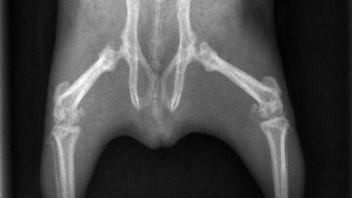

Ich habe sie dann schnell röntgen lassen, mit dem Ergebnis Osteodystrophie. Die Knochen waren schlecht mineralisiert, Wachstumsfugen teilweise nicht geschlossen, Arthrose in den Gelenken. Sie bekam Metacam, damit verschwand die Schonhaltung und sie wurde insgesamt munterer.

Bei Motte trat die OD vor allem in der Hüfte und den großen Hinterbeinknochen auf. Meerschweinchen, die Probleme im Kiefer(gelenk) haben, haben eine deutlich schlechtere Prognose. Platt gesagt, ein bisschen humpeln ist nicht so schlimm wie nicht kauen können.